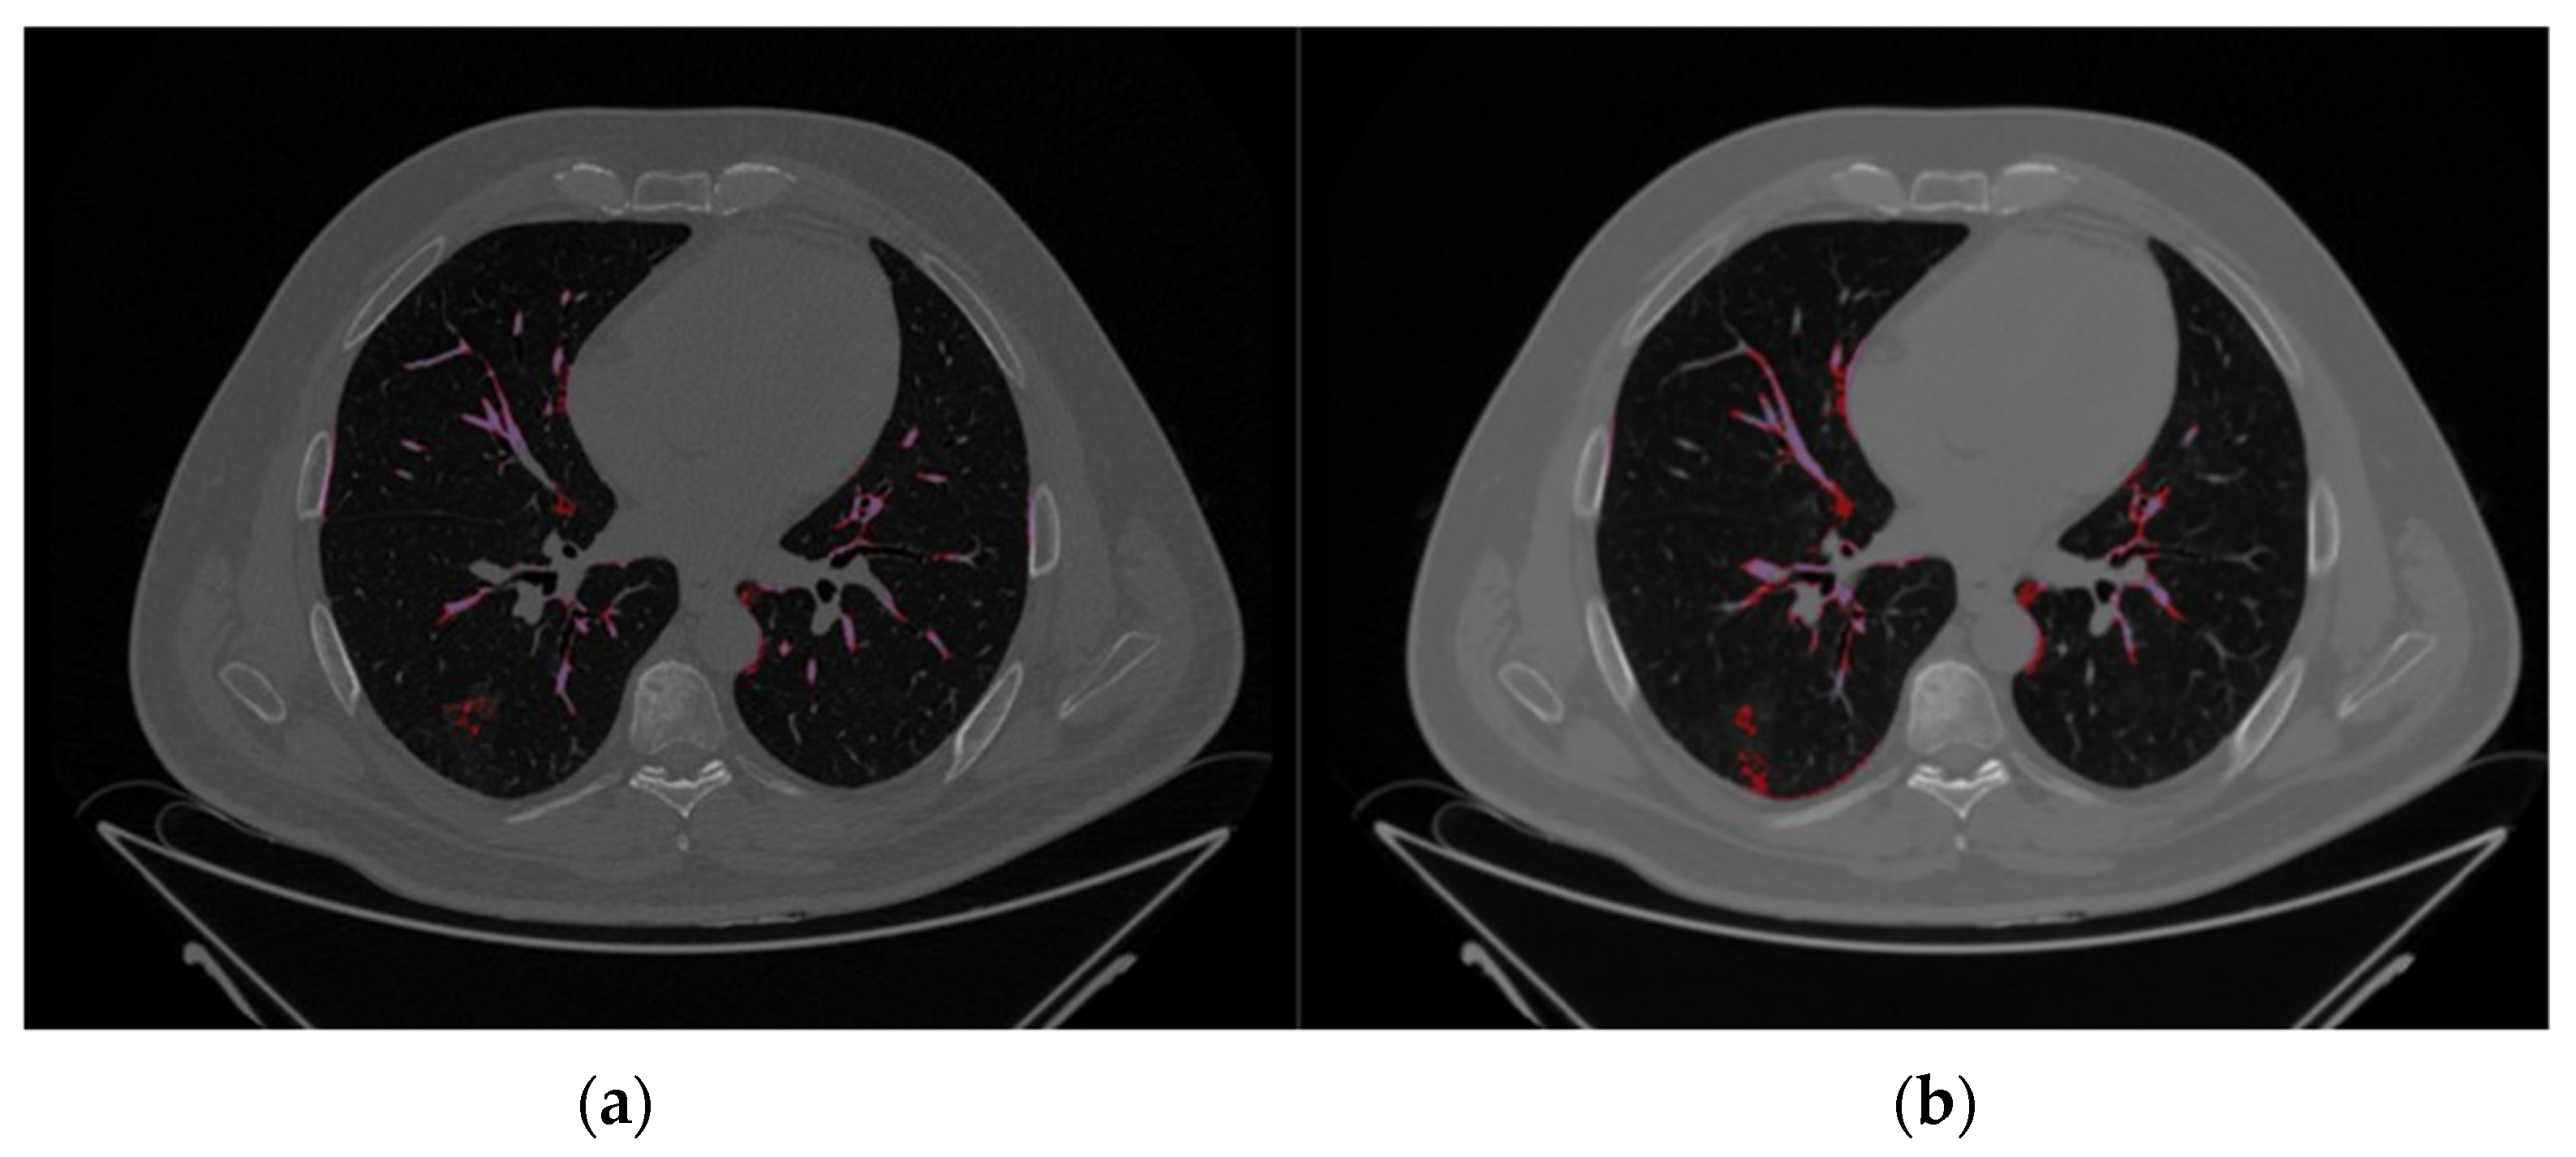

2.2. Image Segmentation and Feature Extraction

3.2. Image Reconstruction and VOI Delineation Results